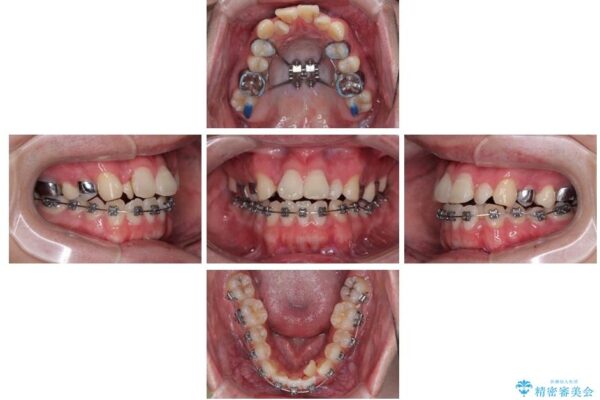

治療方針

このような歯列の狭さに起因するデコボコを改善するために、**MARPE(骨に固定する上顎急速拡大装置)**を使用して、上顎の横幅を拡大し、これにより歯が並ぶためのスペースを確保し、メタルブラケットを用いて歯列を整えていく計画としました。

費用面を考慮し、装置はコストパフォーマンスに優れたメタルブラケットを選択。見た目よりも機能と効果を重視したい方には特におすすめの選択肢です。

治療途中

• 1年でここまで変わる!歯列のがたつきと正中のズレを改善した矯正治療(メタルブラケット×MARPE) 治療途中画像